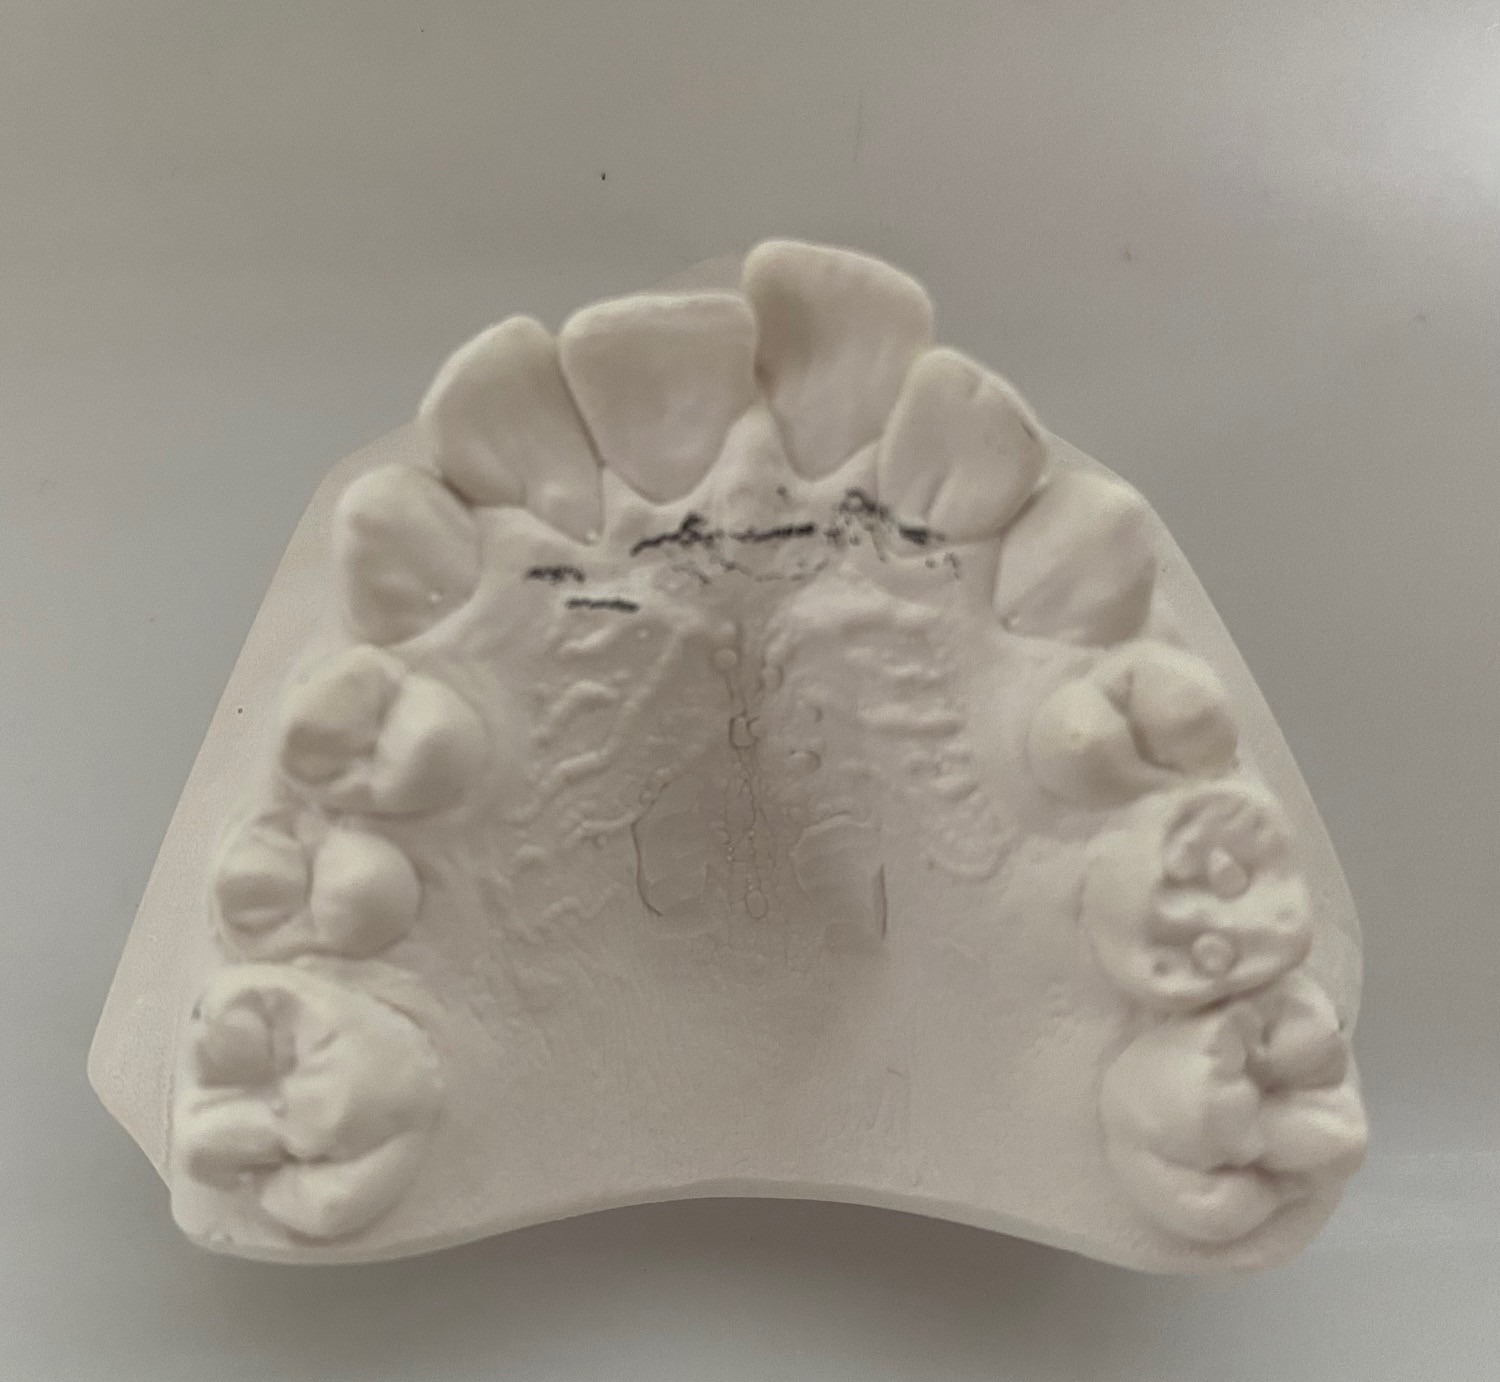

Oppstart med dokumentasjon

Vi tar nødvendige røntgenbilder, foto og kliniske modeller/skanninger. Dette danner det faglige grunnlaget for en individuell behandlingsplan og sikrer korrekt beregning av refusjon fra Helfo.